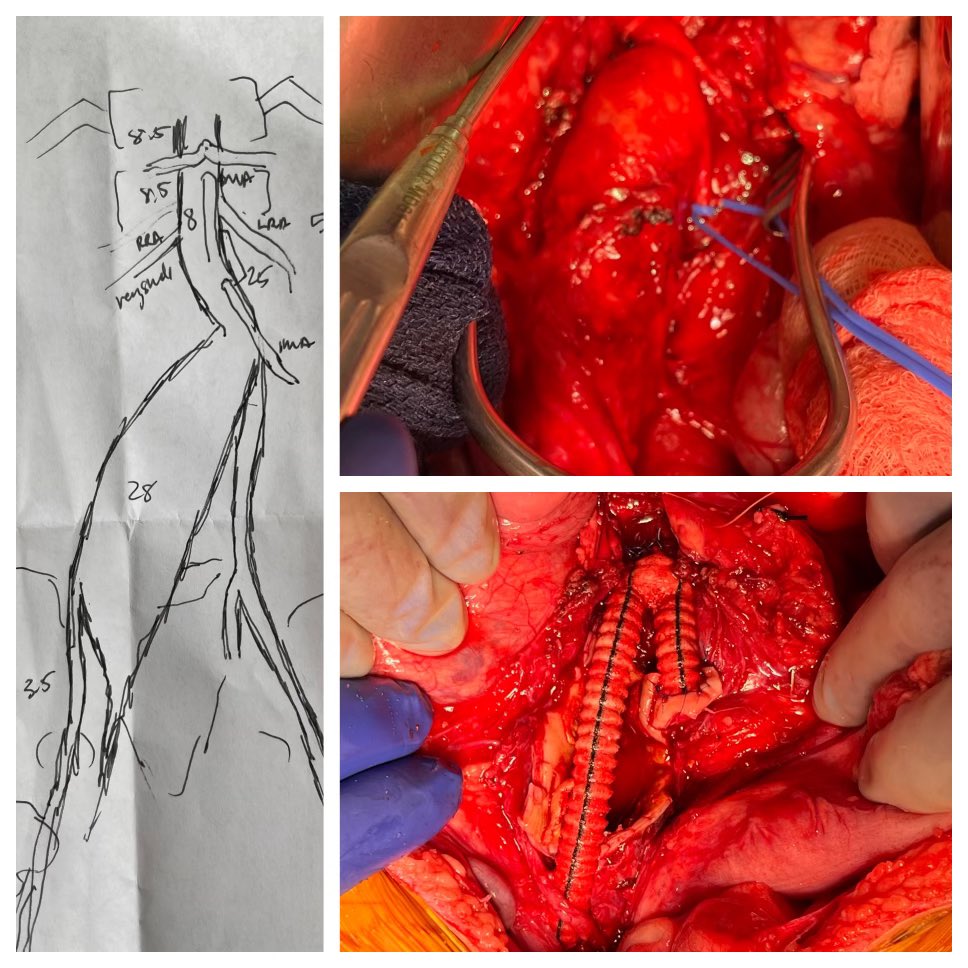

TAAA with arch involvement and previous aorto bi-femoral bypass (left limb occluded): First stage Endovascular total arch repair with physician-modified endograft with a TEVAR extension. Scheduled for a second stage FEVAR.